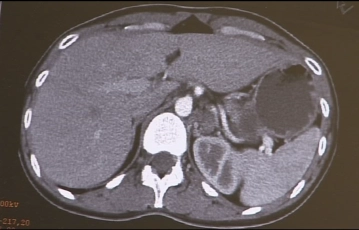

Imaging demonstrates a multinodular 5cm–6cm large cyst-like mass in the region of the left adrenal, clinically confirmed as pheochromocytoma.

CT findings